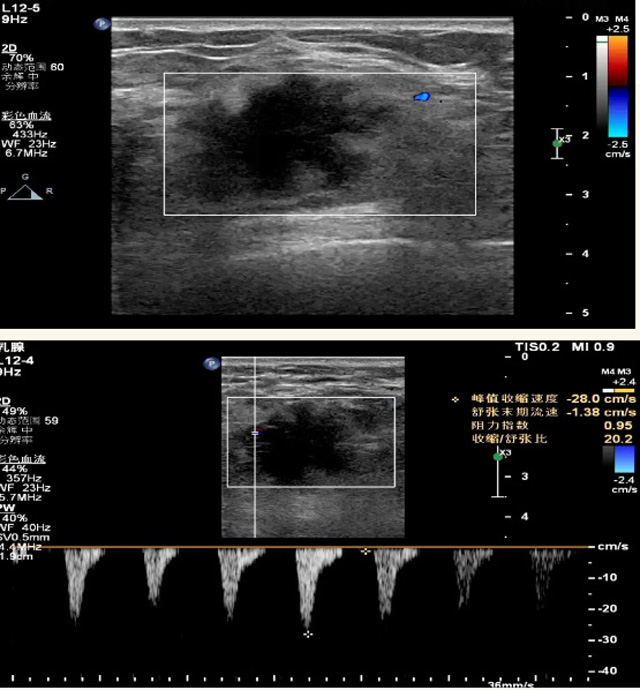

乳腺B超磁共振MRI对乳腺的检查效果怎样?

乳腺B超检查无辐射,对囊性病变敏感,可以实时观察病灶。超声引导活检跟手术前的定位。就是它对于微小的钙化查出率比钼靶稍微差点。磁共振MRI检查也是是没有辐射的,对备孕跟已经怀孕的人士比较友好。不用担心这个辐射影响胎儿问题。对乳腺病灶敏感性较高,致密乳腺病灶、乳腺癌的复发,准确鉴别囊性及实性病变??梢园镏俅惨缴卸隙裥浴⒘夹圆”?。但是MRI磁共振对微小钙化不明显,微钙化还是钼靶靠谱点。检查时间比较长,有伪影的影响。费用相对B超,钼靶高很多。

乳腺B超